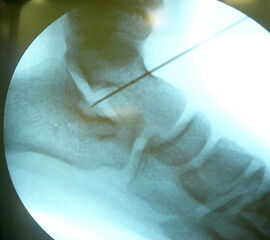

Abwaschen und steriles Abdecken beider Füße in Rückenlage und Unterschenkelblutleere (Abb. 1). Ertasten des Sinus Tarsi, zur genaueren Lokalisation Verwendung einer Kanüle (Abb. 2) um die korrekte Position über dem Eingang zum Sinus tarsi unter Bildverstärker zu kontrollieren. Über einen 1-2cm messenden Hautschnitt (Abb. 3) erfolgt nun die Präparation des Eingangs zum Sinus tarsi durch stumpfe Präparation. Die Knochenoberfläche des Calcaneus am tiefsten Punkt des Sinus tarsi wird dargestellt, unterstützt durch eine manuelle Rückfußinversion. Nach Markieren der korrekten Eintrittstelle mit einem Kirschnerdraht und anschließender Bildwandlerkontrolle (Abb. 4) wird nun die calcaneare Eintrittstelle in ca 20° Kippung nach lateral und dorsal mit einem 3,2mm Bohrer aufgebohrt.

Hierbei ist darauf zu achten, einerseits den Eintrittspunkt nicht zu weit lateral zu wählen um eine Aussprengung der lateralen Calcaneus-Corticalis oder Kompromittierung der Peronealsehnen beim Bohren oder Eindrehen der Spongiosaschraube zu vermeiden, andererseits das Calcaneo-cuboidale Gelenk (C-C-Gelenk) nicht zu verletzen. Nach Gewindeschneiden und Längenmessen Einbringen einer 6,5 mm Titan-Spongiosaschraube mit durchgehendem Gewinde und einer Länge von durchschnittlich 25 bis 35mm. Der Abstand zum C-C Gelenk sollte mindestens 10 mm betragen.